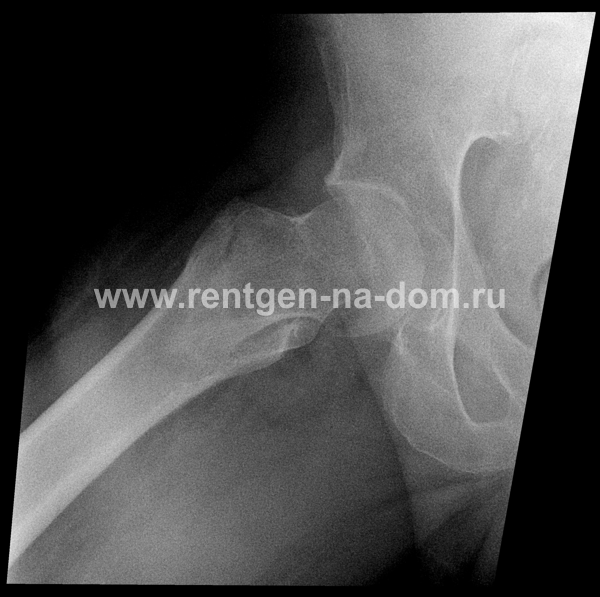

Перелом шейки бедренной кости.

Решающее значение в установлении диагноза перелома шейки бедра имеет рентгенография тазобедренного сустава. У пожилых пациентов приведенные выше симптомы могут проявляться нечетко, а такие заболевания как инсульт или невропатия, вообще, не позволят поставить правильный диагноз без рентгена. Где сделать рентген? Перелом шейки бедра всегда сопровождается сильной болью, поэтому любые лишние движения оборачиваются новыми мучениями, а сопутствующие заболевания внутренних органов усугубляют ситуацию! Решение есть - воспользоваться уникальной услугой – цифровой рентген на дому. К вам приедет врач рентгенолог-травматолог, который выполнит весь комплекс лечебно-диагностических мероприятий и подробно расскажет, что делать дальше.

Получение качественных рентгеновских снимков на дому предъявляет серьёзные требования к рентгеновской аппаратуре. Далеко не каждый переносной рентгенаппарат позволяет получать снимки необходимого качества, чтобы достоверно поставить диагноз. Используемый нами рентгенаппарат АРА 110/160 в комплексе с компьютерным радиографом позволяет получать цифровые рентгеновские снимки высокого качества у пациентов различной комплекции и является уникальной услугой в Санкт-Петербурге, предоставляемой на дому.